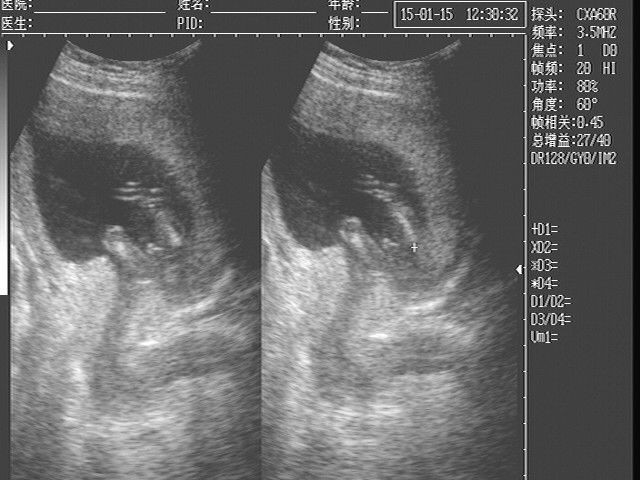

如何判断排卵期?

肛门坠胀,侧下腹痛

女性排卵期,成熟的卵子从卵巢表面冲破滤泡而排出,此时,滤泡内少量液体会因此流入盆腔最低部位。对于较为敏感的女性朋友来说,肛门就会出现轻度的下坠感,或是腹部会出现微痛。

抵抗下降,细菌入侵

排卵期的存在就是为了使精子能够顺利与卵子结合,而此时阴道也相当配合,阴道分泌物会变稀薄,以利于精子更加方便进入女性体内。同时,女性鼻腔粘液分泌也会减少,这样一来,身体防御系统下降,细菌便有了可乘之机。

白带增多,粘稠度小

白带多为无色无味的粘液,主要是起到湿润阴道、排泄废物、抑制病原菌生长的作用。排卵期的女性白带会明显的增多,呈稀薄乳白色,若用手纸擦时会发现鸡蛋清样条状黏液。这是因为排卵期,宫颈在雌、孕激素作用下,宫颈口开张并且会分泌大量粘液,如蛋清样,粘稠度最小,排卵结束后,粘液会迅速减少,变稠。

下腹微痛,为排卵痛

月经来潮可能会出现痛经症状,而排卵期也会出现轻微的下腹疼痛,这叫排卵痛。有时也会伴随一定的胸部胀痛,但是排卵痛一般并不明显,大约有1/3妇女有排卵痛。这是因为女性排卵时,体内前列腺素的增加,卵泡液腔的压力增大,卵巢表面要发生破裂使卵子排出,这一破裂的过程对一些敏感的妇女会产生下腹疼痛。有时为激烈疼痛或持续性钝痛,可持续6-12小时。